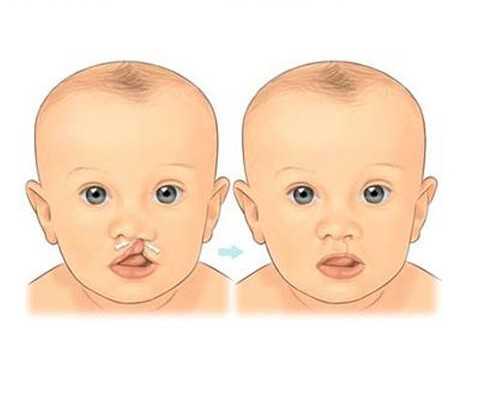

現在越來越多女性非常重視備孕的過程,備孕的整個過程對于健康環境來說具有重要影響,除了會讓你更順利輕松的懷孕之外,還能讓寶寶的發育更為健康,避免在懷孕階段出現各種意外情況,針對備孕需要檢查宮腔鏡嗎這個問題是很多女性比較注意的,建議大家需要了解下哪些問題,才能確定備孕檢查是否需要進行宮腔鏡檢查。

1、根據自身情況選擇檢查項目

備孕整個過程也是需要進行全面檢查,只有這樣才能確定自己身體情況是否符合生育的要求,避免在懷孕階段出現各種意外情況,關于備孕是否需要進行宮腔鏡檢查,最主要還是要結合自身的情況來進行判斷,因為只有確定自己身體,是否需要進行檢查,才可選擇宮腔鏡進行檢查,建議需要了解這些問題。

2、宮腔鏡檢查的主要目的

宮腔鏡檢查的主要目的是為了更好的確定子宮環境,同時也想更好的判斷子宮內膜的情況,尤其是對各種婦科疾病治療會有一定的促進效果,但是如果經過檢查沒有非常嚴重的婦科病,之前沒有過流產的情況,在整個備孕階段沒有長時間不能受孕,通常不需要這樣的檢查。

3、保證健康懷孕的技巧

如果想更健康輕松順利的懷孕,如果確實需要宮腔鏡檢查,建議必須要配合醫生的要求,進行宮腔鏡檢查,醫生給出的意見肯定是非常專業健康安全的,也都是對你身體有好處的,所以不要質疑醫生的決定,做宮腔鏡檢查之后卻是半年之內不能懷孕,但這并不代表以后就不能懷孕,檢查清楚確定疾病,針對性治療才能給你帶來更好的懷孕優勢,否則就會很快懷孕了,也沒有任何意義。

在懷孕之前需要做好全面充分的檢查,尤其是要注意積極的進行備孕,這樣才能保證你懷孕的過程更加健康,避免在懷孕階段出現各種問題,建議要綜合考量以上這些細節,同時會考量備孕需要檢查宮腔鏡嗎,這樣才能確定自己在備孕階段要注意哪些事情,這對調理身體備孕來說會有很好的效果。